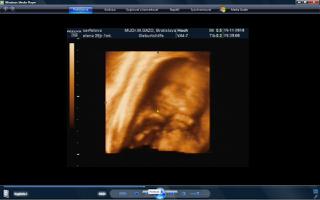

vcera som mala poradnu a teda dopadla pre mna dost prekvapujucu. mala je uz mesiac otocena dolu hlavickou a tlaci sa a tlaci. krcok sa mi zacal skracovat, ale zatial sa neotvara. a aby toho nebolo malo, tak mam aj iritabilnu maternicu. buducu nedelu idem do nemocnice na premeranie krcka a uvidi sa, co bude. aspon, ze ju uvidime 3D potvorku malu nedockavu 🙂 do mesiaca mi zrejme bude treba zaviest pesar.. tooolko radosti naraz a to som povodne vobec nemala mat poradnu, kedze som povodne dosla len s babkou na kontrolu..tak vysetrila aj mna.

caute baby. uz som tu dlho nebola. nejako nestiham. My sme uz boli na tiez na 3D a zase mala mala rucicky pred tvarickou ale daco bolo aj vidno. takze sme zistili, ze sa podoba na muza, teda aspon ten nos usta. Ma skoro 500 g takze je asi o tyzden posunuta neskor.Ak sa mi bude dat tak pridam dake fotky z toho dvd co som vybrala. Inac ja som kupovala tehotenske pancuchy v Brendone v Ba za 4 Eura. teda tenke ale mali tam aj hrubsie a tie stali 15 eur. Ja tiez rozmyslam rodit v ruzinove ale asi skor na Kramaroch. to mam blizsie domov. Ja si doplacam od marca dobrovolne nemocenske poistenie k povinnemu do maximalneho vymeriavaceho zakladu, aby som mala maximalnu matersku. Takze snad s tou materskou sa to bude dat ale horsie to bude s tym rodicovskym prispevkom.